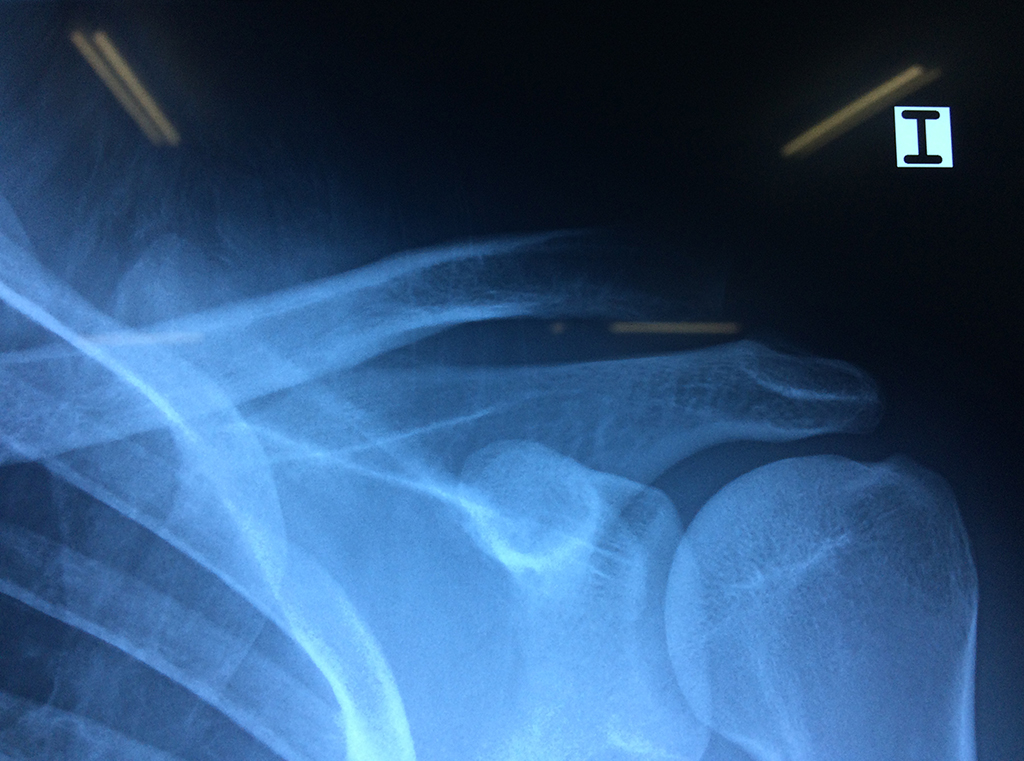

En anatomía humana, el hombro es la parte del cuerpo donde se une el brazo con el tronco. Está formado por la conjunción de los extremos de tres huesos: la clavícula, la escápula y el húmero; así como por músculos, ligamentos y tendones.

La principal articulación del hombro es la que une la cabeza del húmero con la escápula, recibe el nombre de articulación escapulohumeral y presenta dos superficies articulares, una de ellas corresponde a la cabeza del humero que tiene forma semiesférica y la otra es la cavidad glenoidea de la escápula, estas superficies están recubiertos por cartílago que permiten un movimiento suave e indoloro.